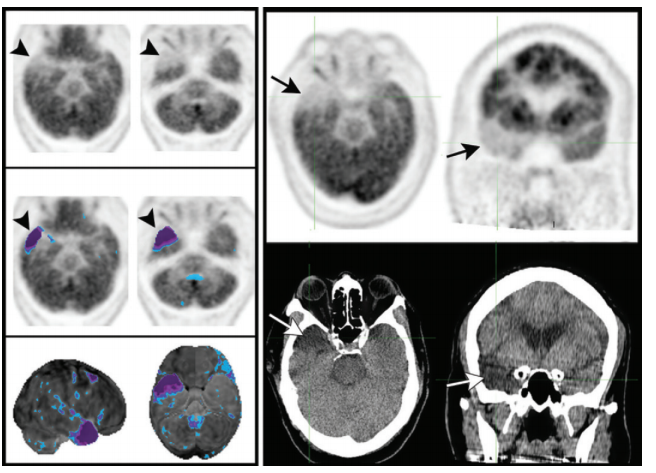

atrophy –> sulcal widening –> artifact of hypometabolism (pitfall for misdiagnosis of neurodegenerative disorder)